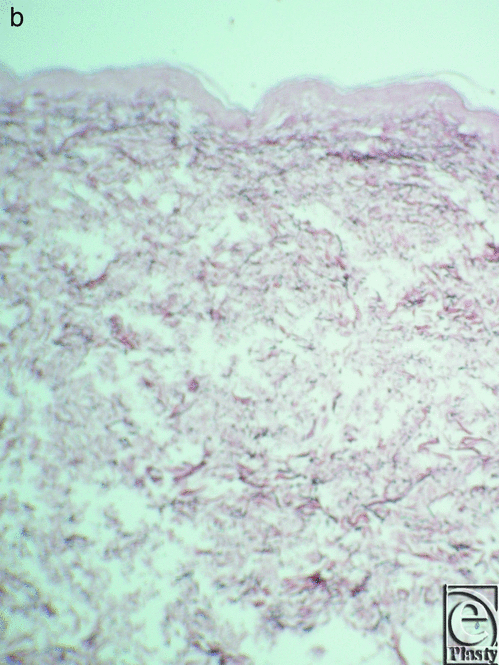

The skin specimens superior and inferior to the skin creases assert that collagen and elastic fibers have a rather random pattern compared with the well-organized network of the fibroelastic bundles in the skin of the creases sites. The elastic fibers are fewer and have a parallel pattern in the dermis (Fig 12a) in the skin inferior and superior to the infragluteal crease and are fewer in number and placed in a parallel pattern in the dermis (Fig 12b) in the skin superior and inferior to the inframammary crease.

This study has included the histological comparison of the skin superior and inferior to the crease sites with the crease specimens. The collagen and elastic fibers have a rather random pattern, whereas at the crease site, there is a particularly organized network of fibroelastic bundles.

Creases of the trunk are formed by well-organized collagen bundles in a beehive pattern, attached to the dermis and related to the underlying muscle fascia. The anterior axillary fold has less organized collagen bundles and elastic fiber participation and orientation. The elastic fibers participate in the formation of the collagen network and radiate in a parallel fashion in the reticular dermis and in a perpendicular pattern in the papillary dermis. The skin superior and inferior to the creases lacks such organization of the collagen and elastic fibers and is deposited in a random pattern.